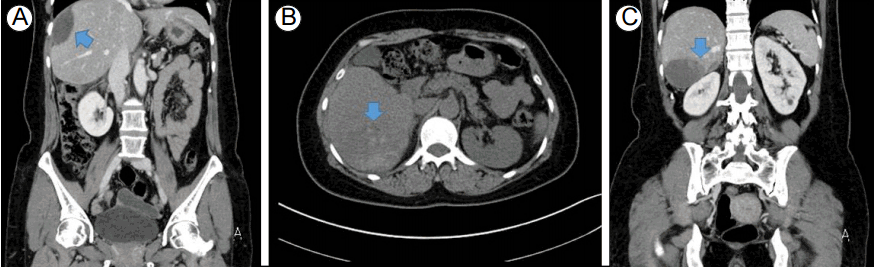

Figure 2.

Computed tomographic finding at 2 months later. Previously observed large subcapsular hematoma was absorbed, and size was decreased. However, another 8.8 cm sized subcapsular hematoma was observed in the right liver, segment 6 area. (A) coronal view of computed tomography showing decreased size of previously observed hematoma, (B) transverse view and (C) coronal view of newly developed subcapsular hematoma. The arrow points to the edge of the subcapsular liver hematoma on the image.